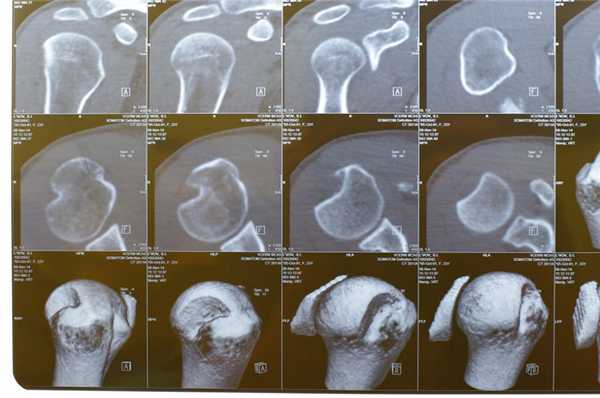

При компьютерной томографии выявлена диффузно-глыбчатая оссификация капсулы сустава по медиальной поверхности (на 8-12 часах условного циферблата головки плечевой кости по сагиттальным снимкам) на участке размерами 1,5х0,7х4,5 см плотностью от 200 до 890 HU (средней плотностью ~ 300 HU), медиальных отделов субдельтовидной сумки, в зоне малого бугорка (в области фиксации сухожилия подлопаточной мышцы), более «нежная» по капсуле вокруг вертикального сегмента сухожилия длинной головки бицепса; отсутствует в области фиксации остальных сухожилий ротаторной манжеты к большому бугорку и в самом сухожилии длинной головки бицепса (рис. 3). Данный характер оссификации также подтверждает представления о фазном характере течения рассматриваемой патологии.

Рис. 3. КТ левого плечевого сустава пациентки Л., 50 лет (март 2019 г.). Аксиальный срез (а) на уровне верхней части головки плечевой кости: бобовидной формы крупный кальцинат по медиальному контуру головки плечевой кости в зоне расположения капсулы; МПР-корональный срез демонстрирует расположение кальцинатов по капсуле вдоль вертикального сегмента сухожилия длинной головки бицепса (б), МПР-сагиттальный срез весьма наглядно показывает локализацию кальцинатов по капсуле и в зоне субдельтовидной сумки (в) и 3D реконструкция правого плечевого сустава в объемном представлении детализирует патологическое состояние в мягкотканых структурах сустава (г). Визуализируется оссификация капсулы вокруг сухожилия бицепса; кальцинаты в подклювовидном и субдельтовидном пространствах